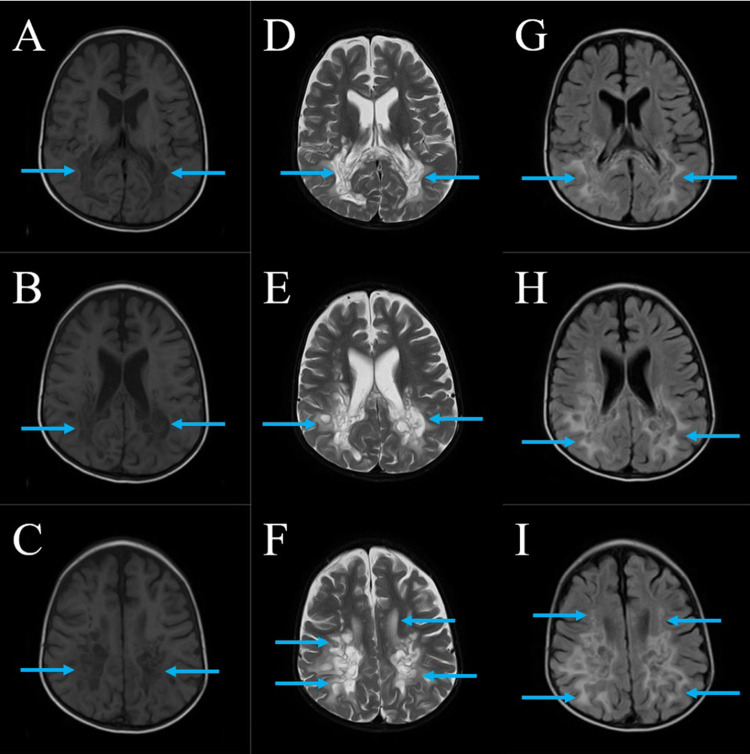

Case presentation: We present a case of a 10-year-old boy with ALD who presented with seizures, progressive weakness, visual impairment, and adrenal insufficiency. Despite symptomatic management and dietary adjustments, the disease progressed rapidly, leading to respiratory failure and eventual demise. The diagnosis was confirmed through molecular analysis and elevated VLCFA levels. Neuroimaging revealed characteristic white matter changes consistent with ALD.